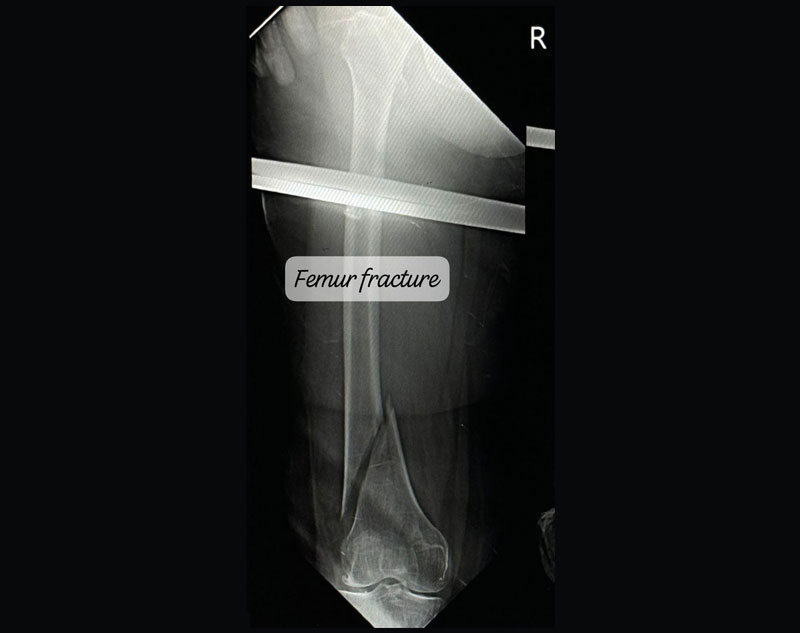

Fracture refers to the breaking or cracking of a bone. It occurs when the bone is subjected to more force than it can absorb.

Complex Trauma in orthopedics refers to severe injuries involving multiple or complicated fractures, often combined with soft tissue damage.